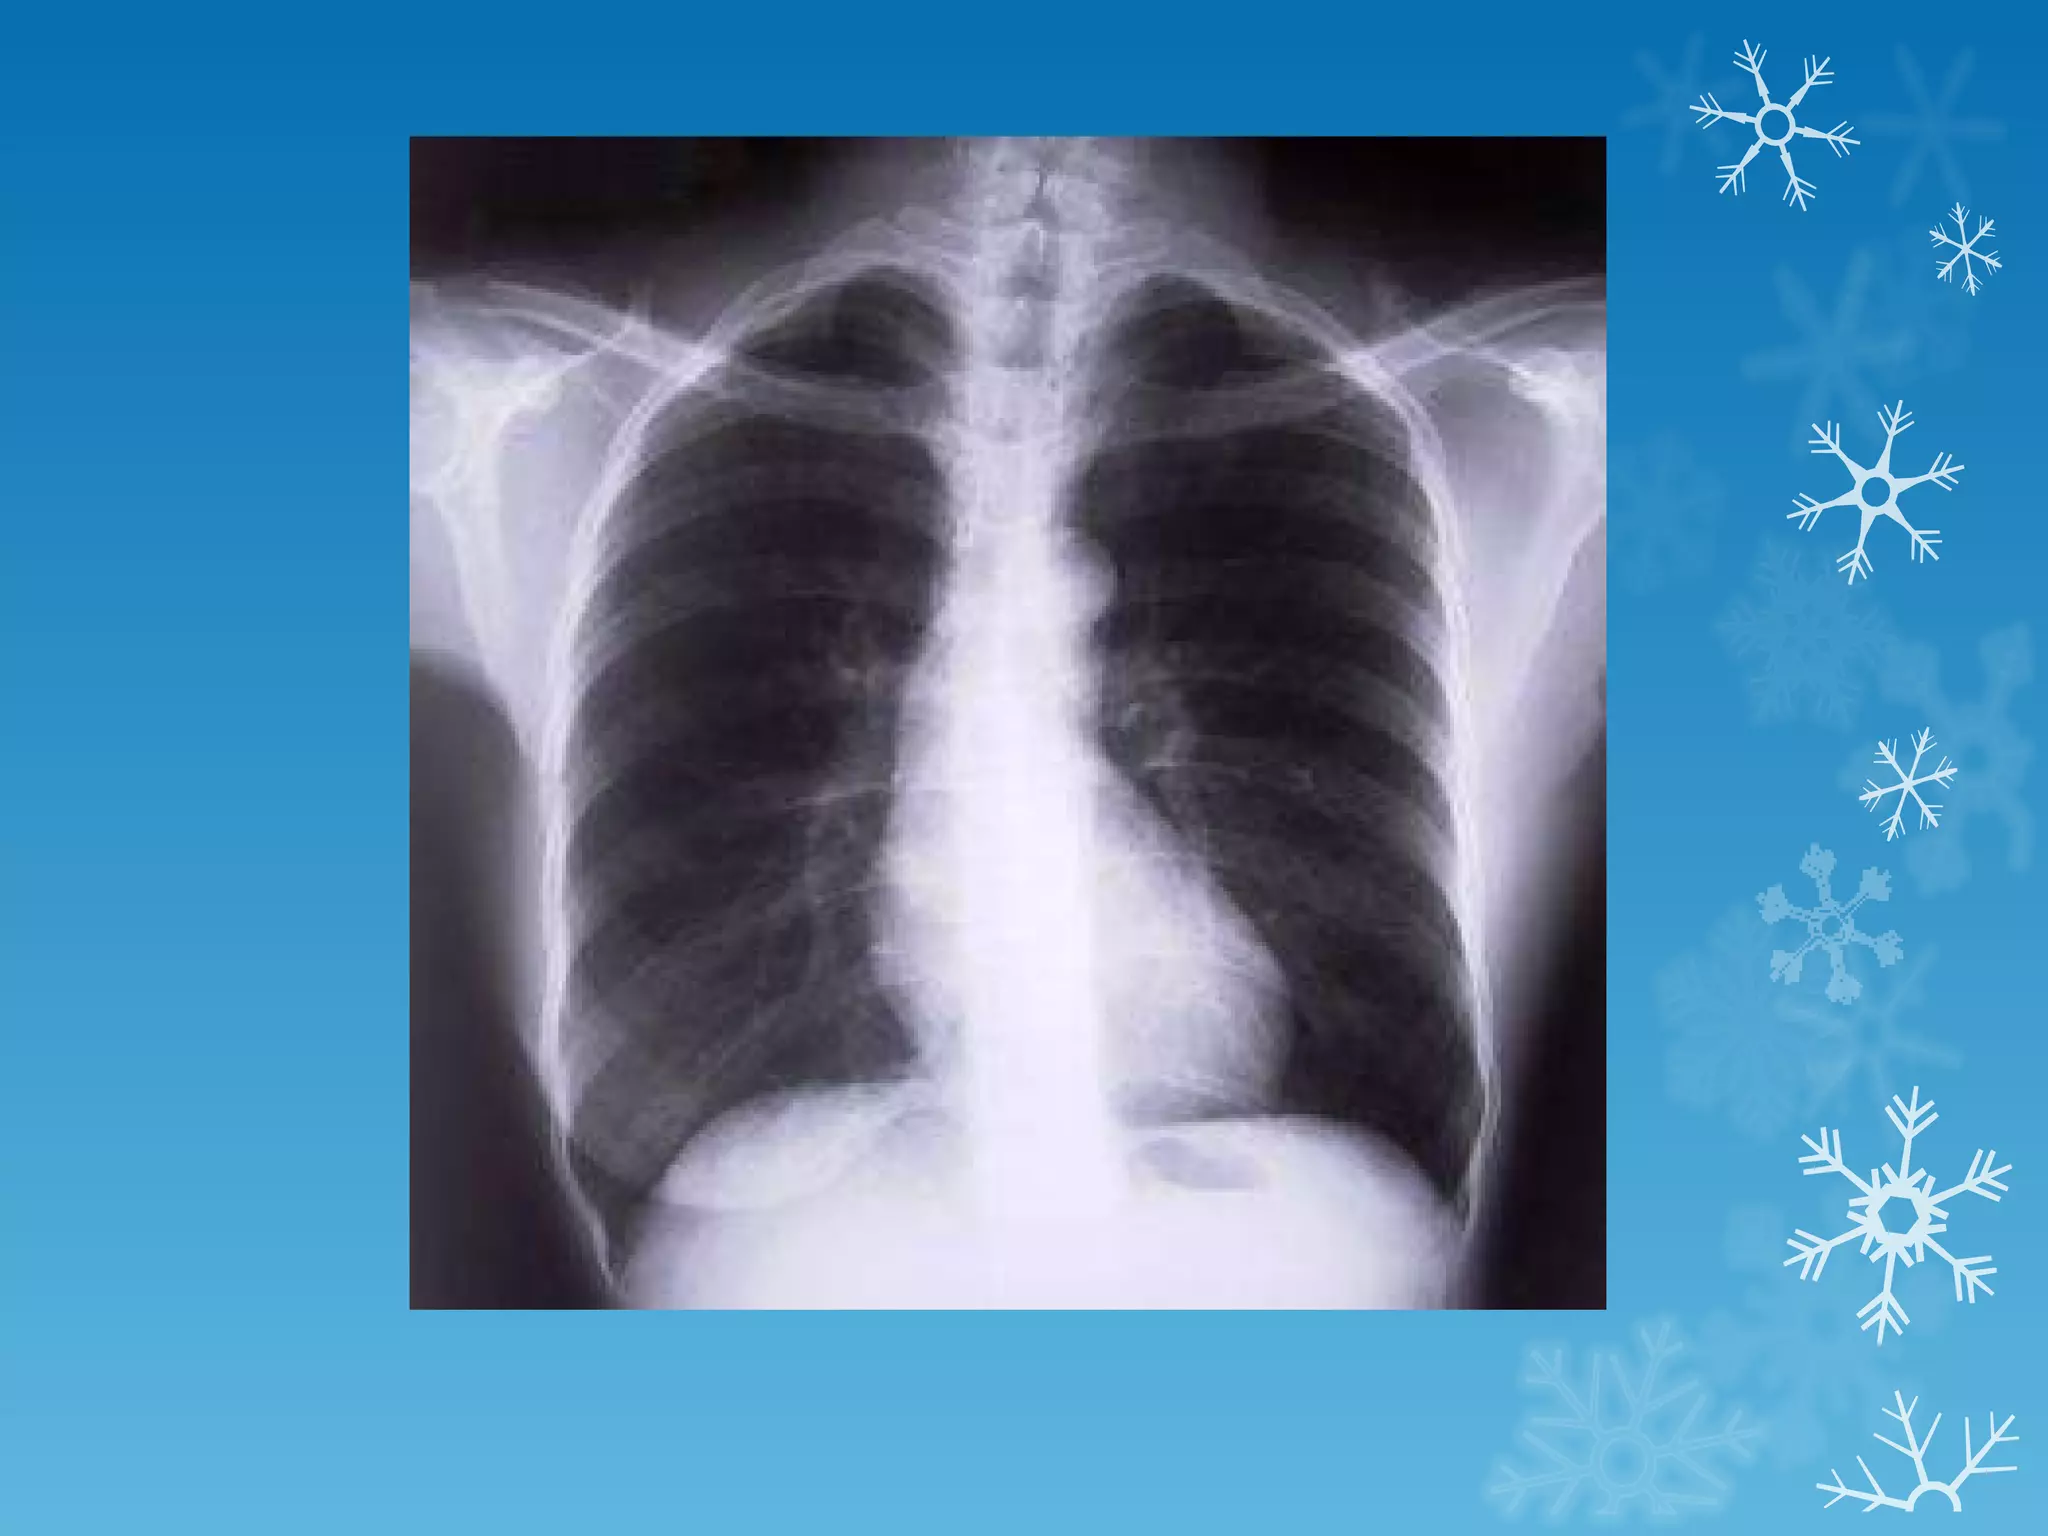

This document discusses chest x-ray interpretation and provides guidance on evaluating x-rays. It explains that tissue density determines how an x-ray beam penetrates, with denser tissues appearing whiter and less dense tissues appearing blacker. It also outlines different chest x-ray views and factors to consider like patient orientation, age, gender, and rotation. Abnormalities are described as appearing too white, too black, too large, or in the wrong place. The document stresses a systematic approach of identifying, localizing, describing lesions, and providing differential diagnoses.